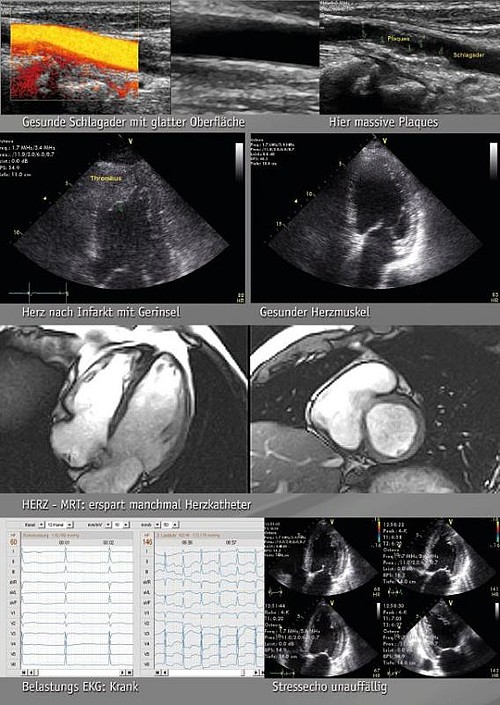

Echokardiographie / Herz-MRT (Cardio-MRT)

Ultraschalluntersuchung des Herzens / Untersuchung mittels der Magnetresonanztomographie ohne Strahlen

Stressechokardiographie

Untersuchung des Herzens während der Belastung/Stimulation, Physikalische Belastung (auf einer speziellen Fahrradliege)

Doppler/Duplexuntersuchung

der hirnversorgenden Arterien, Ultraschalluntersuchung der Gefäße, die das Gehirn mit Blut versorgen

Belastungs-EKG

Aufzeichnung der Stromlinien des Herzens während der Belastung

Doppler/Farbdopplerechokardigraphie

Untersuchung des Blutflusses im Herzen